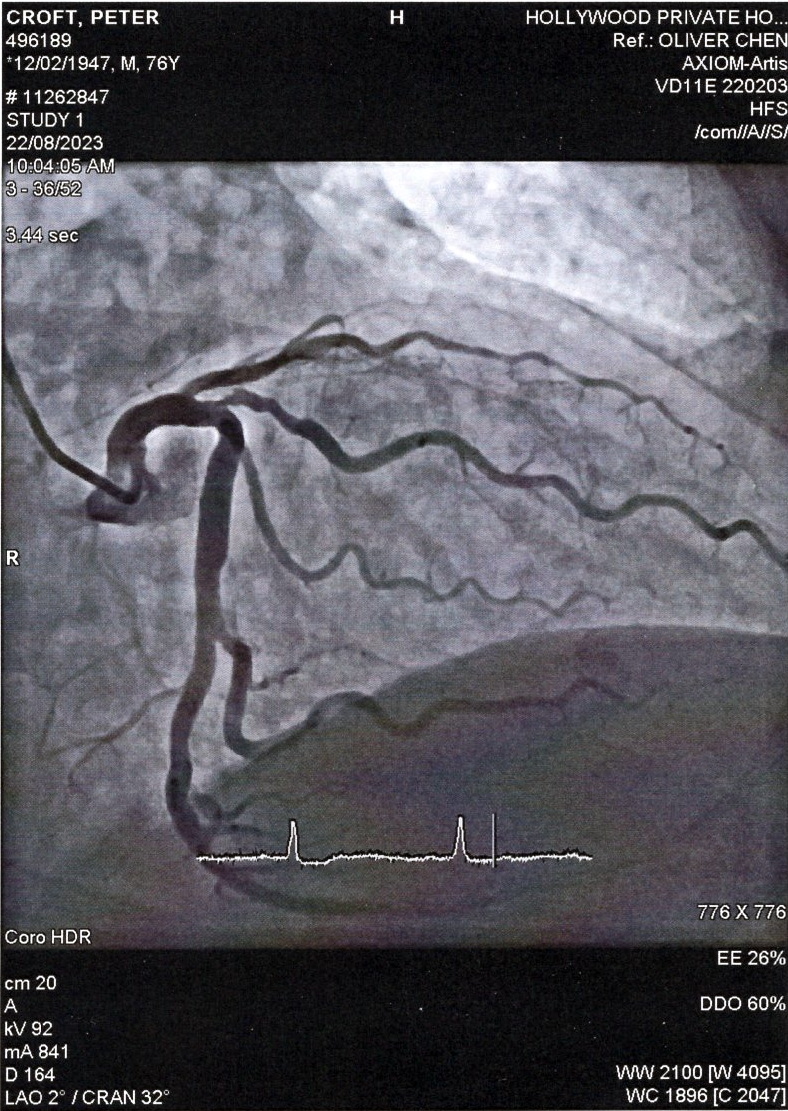

In the end I wasn’t wheeled into the refrigerated! operating theatre until 10am. All went smoothly and as you can see, he didn’t find anything remarkable, although there is one narrowed bit apparently. I have to see the cardiologist in six weeks, so I’ll find out more then.

I must admit to feeling very poorly in the past few weeks. Weak and tired. I’ve been getting a bit of angina and puffs of breathlessness. I saw the cardiologist last week and he wants to do an angiogram (I call it an angrygram 🙂 ), so that’s going to happen on Tuesday 22nd, Tuesday week. I don’t like these procedures (probe up through an arm vein into the heart!), but last time he did one on 26 January 2021, he found a 90% blocked vein. Lucky! So it needs to be done.